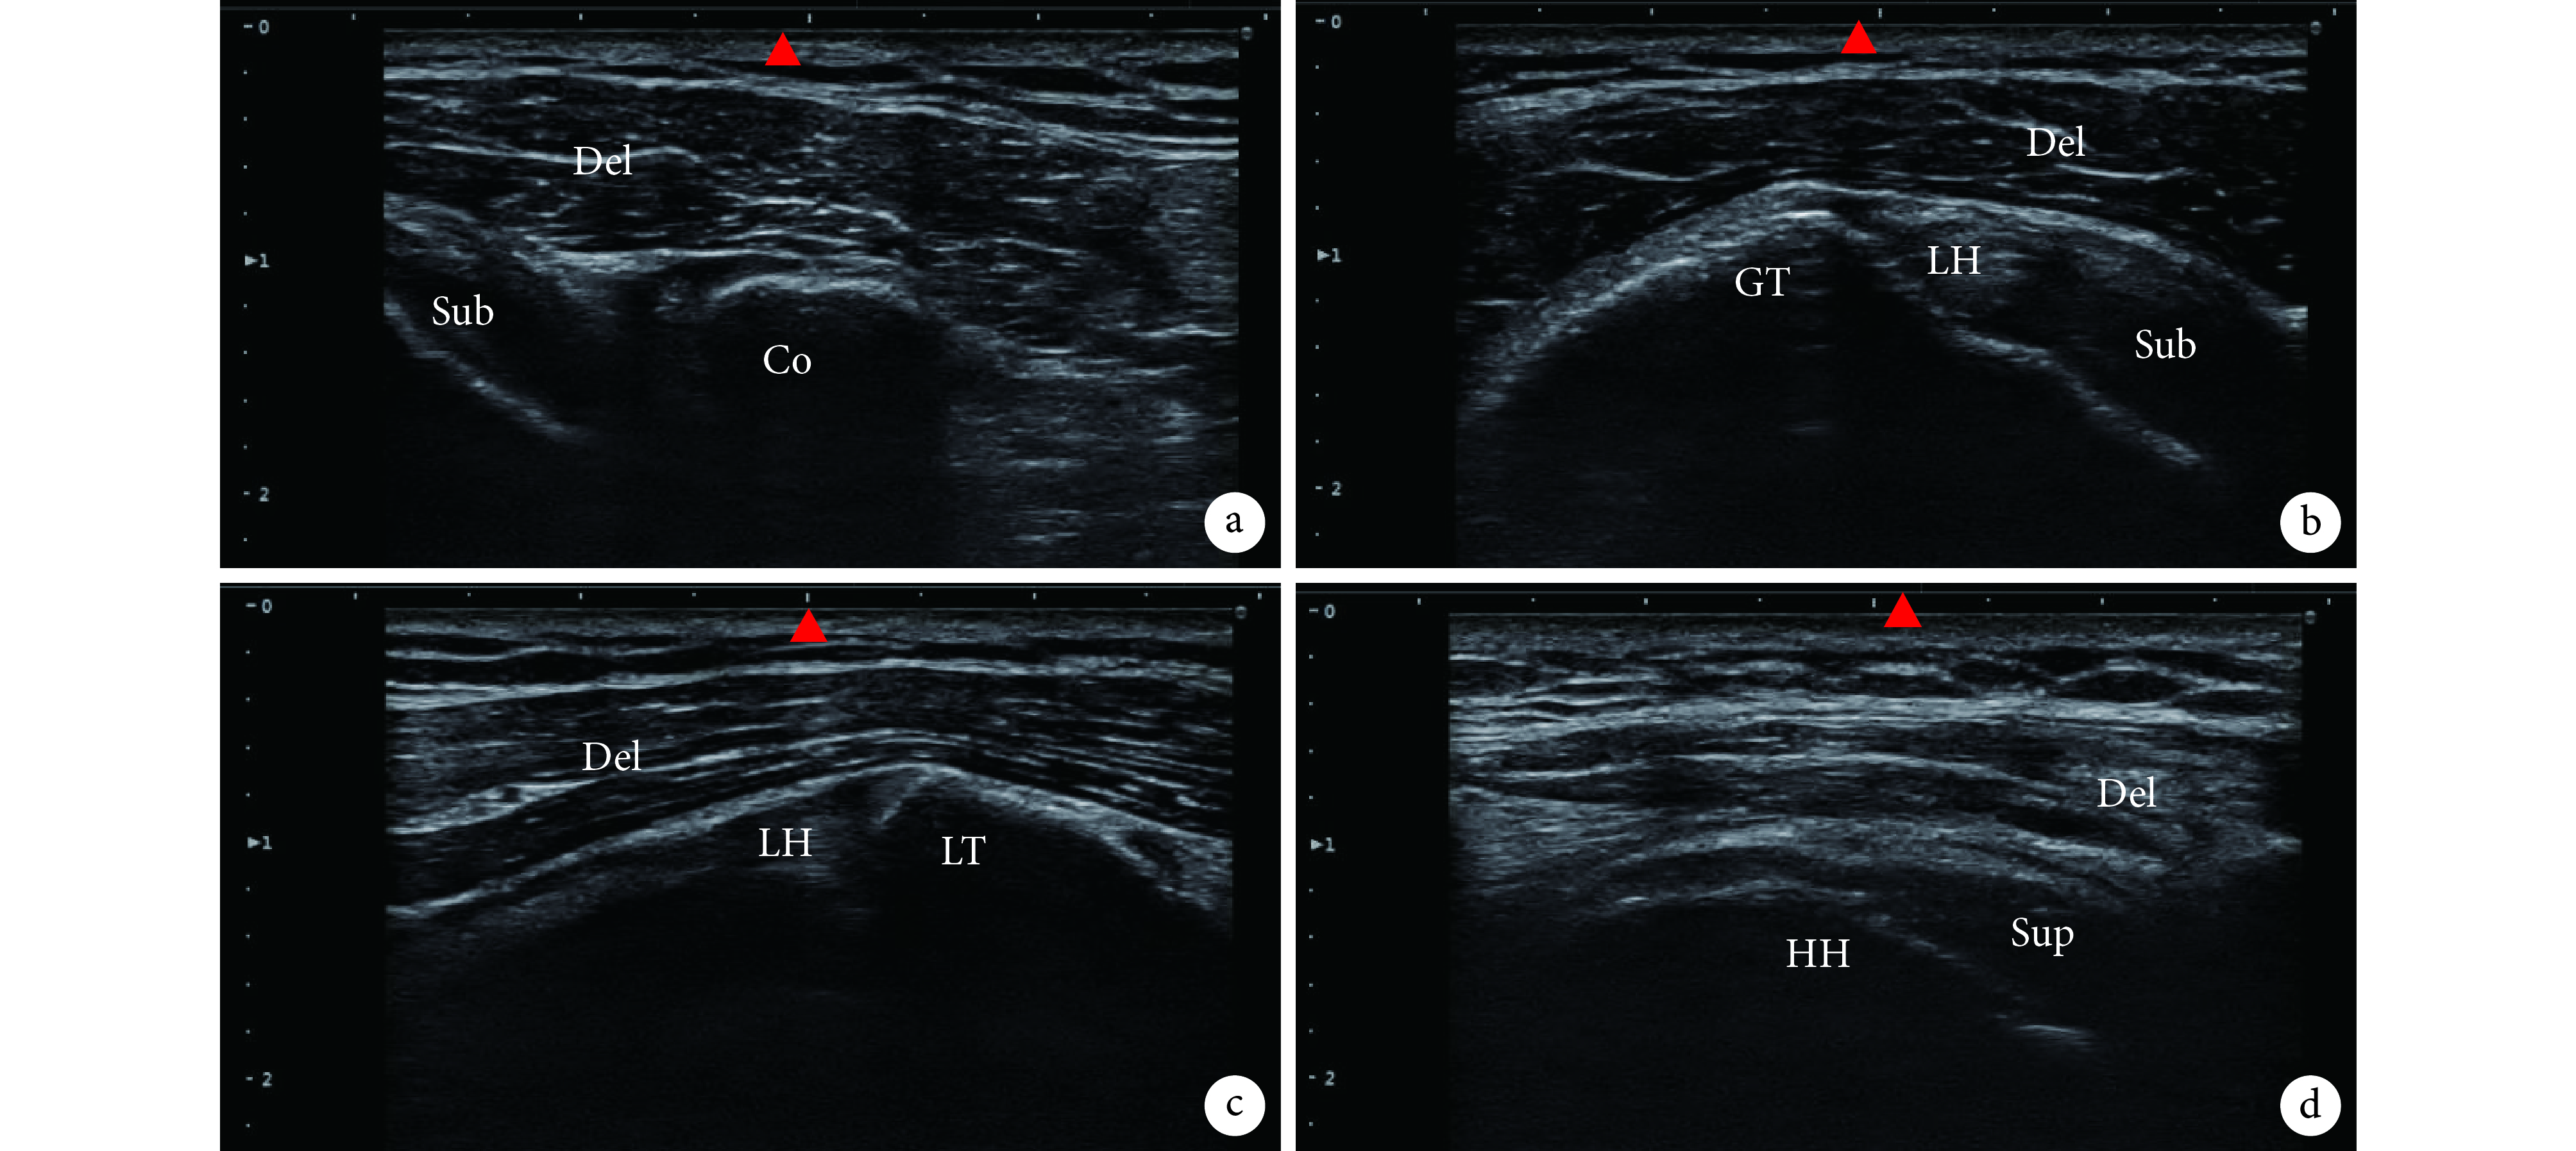

徒手定位 4 個點(圖 1),高頻超聲掃查定位點處結構(圖 2)后發現,42 例患者所有進針點定位準確率高,均為 100%。

圖中探頭中央位置(▲)與體表定位點一致。Del:三角肌;Sub:肩胛下肌腱;Co:喙突;GT:肱骨大結節;LH:肱二頭肌長頭肌腱; LT:肱骨小結節;Sup:岡上肌肌腱;HH:肱骨頭。a. 喙突點;b. 肱骨結節間溝點;c. 肱骨小結節點;d. 三角肌下滑囊點